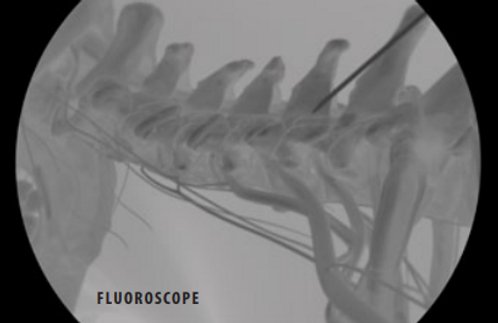

fluoroscope

Inserting the Cannula

The physician inserts a tube called a “cannula.” A video x-ray device called a “fluoroscope” helps guide the cannula to the medial branch nerves in your spine. These tiny nerves carry pain signals from your facet joints to your brain.